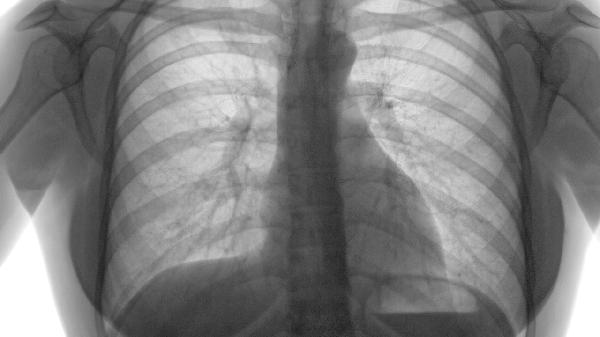

肺结节分为实性、磨玻璃和部分实性三类,其中部分实性结节恶性概率最高约7%-10%。直径小于6毫米的结节恶性率低于1%,而大于8毫米的结节需结合PET-CT或穿刺活检进一步评估。随访观察中结节体积倍增时间小于400天需高度警惕。

吸烟指数超过20包年、有恶性肿瘤家族史、接触石棉或氡气等职业暴露人群风险显著增高。结节边缘毛刺征、分叶征、胸膜牵拉等影像学特征提示恶性可能,需结合肿瘤标志物如CEA、CYFRA21-1辅助诊断。